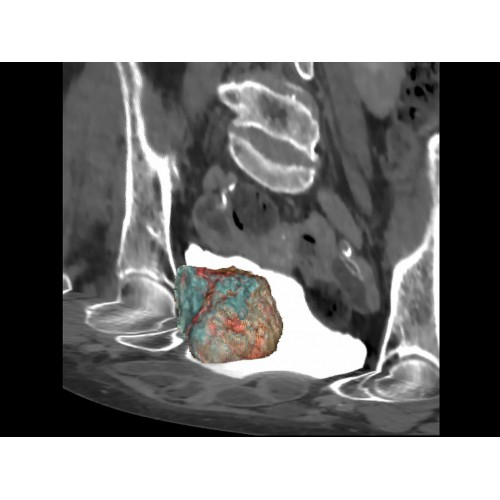

Онкология

• Раннее выявление новообразований и контроль эффективности лечения.

• Планирование лучевой терапии с высокой точностью.